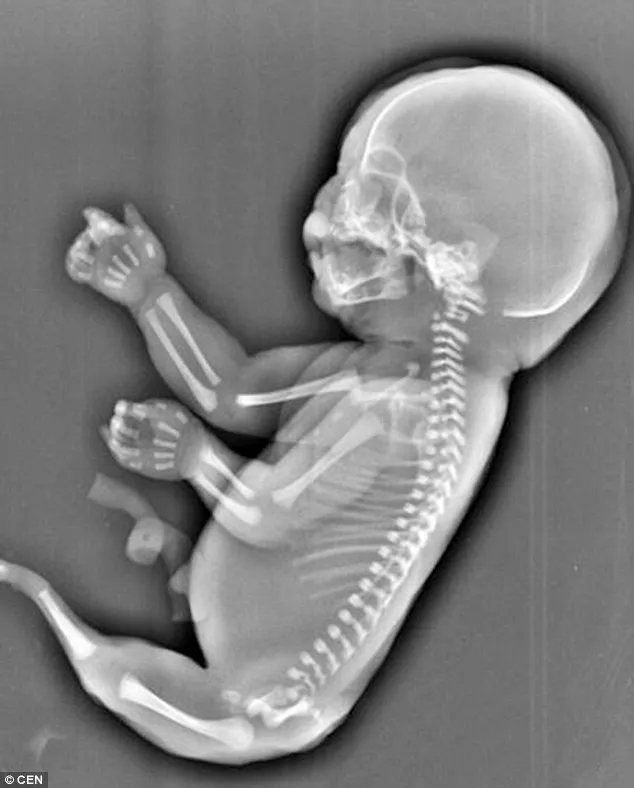

Cô Wu, 23 tuổi, sống ở tỉnh Hồ Bắc, miền Trung Trung Quốc. Cô Wu đã mang thai được sáu tháng. Sau khi xét nghiệm, bác sĩ cho biết thai nhi không có hai chân mà thay vào đó là một “cái đuôi” đang phát triển.

Thai nhi cũng không có bàng quang và có một lá gan còi cọc. Ảnh: Internet

Thai nhi cũng không có bàng quang và có một lá gan còi cọc. Các bác sĩ nói với cô Wu rằng thai nhi mắc phải hội chứng người cá còn gọi là “hội chứng người cá”, một dị tật bẩm sinh hiếm gặp, hai chân dính liền với nhau trông như một đuôi cá.

Mặc dù đã mang thai được nửa năm, cô Wu vẫn quyết định phá bỏ bào thai sau khi các chuyên gia ước tính rằng đứa bé chỉ sống được một vài giờ sau khi sinh ra. Nguyên nhân của "hội chứng người cá" vẫn là một bí ẩn y học và trong 100.000 trường hợp mang thai chỉ có một trường hợp mắc phải.